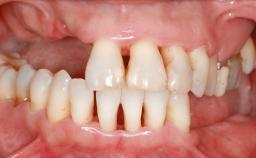

A 20-year-old woman was referred for implant therapy in 2004. Her medical history revealed no significant findings, and neither did she smoke nor take any medications. An extraoral examination revealed no abnormalities of the skin, hair or nails. The intraoral examination revealed only 11 permanent teeth clinically. These were normal in shape, size, and color. In addition, eight retained deciduous teeth (53, 62, 63, 71, 72, 73, 81, 82) were present. No abnormalities were detected during the general examination. The family history revealed that the patient’s father and two sisters were on record with similar conditions. The clinical examination revealed a thick gingival biotype. No recession of the attached gingiva was noted, but the retained deciduous teeth were mobile and unsightly. As a syndrome had not been diagnosed, the case was categorized as non-syndromic oligodontia.

Case Type Extended Space

Jaw Maxilla and Mandible

Area Anterior|Posterior

# of Teeth 14